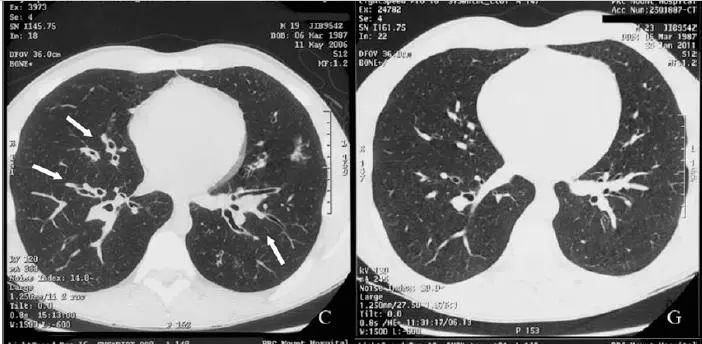

He adhered to treatment and significant improvement in symptoms was noted over 6

months. At a review 2 years later, he had complete resolution of symptoms and further improvement in spirometry values , and repeat high-resolution computed tomography showed no evidence of previously noted dilated airways.

病人坚持治疗,6月后症状好转,2年后,各方面都好转,连支气管扩张都好了!

This case highlights the fact that not all radiological postinfective bronchiectatic changes should be considered as irreversible.Early effective therapy should be provided and the patient monitored for resolution。

事实胜于雄辩,影像学发现的支扩,并不都是不可逆的。早期治疗,随访,有希望缓解。

下面是作者提供的精彩图谱,什么时候,国内的文献也有图,有稍微清晰一点的图。